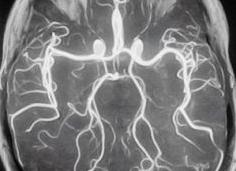

С помощью магниторезонансной ангиографии диагностируют сосудистые патологии, в процессе процедуры применяют магниторезонансный томограф. Под влиянием радиочастотного импульса и магнитного поля прибора изменяется магнитное поле атомов водорода в жидкостях, в данном случае в крови, так как она обладает другой химической структурой в сравнении с неподвижными тканями (костной, мышечной). Эти кратковременные изменения энергии фиксируются в виде изображений.

Пример магниторезонансной ангиограммы

Прибор регистрирует информацию о скорости движения крови в сосудах. На участках, где имеется нехарактерное сужение или расширение, скорость кровотока замедляется или ускоряется, обозначая расположение патологии.

Таким образом, благодаря разным видам МР ангиографии (фазово-контрастной, времяпролетной, 4Д) получают двухмерные или трехмерные изображения не самих сосудов, а циркулирующей по ним крови.